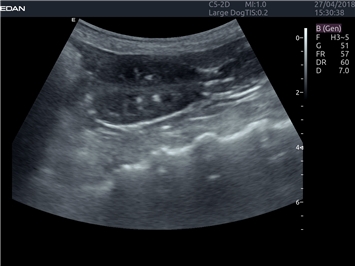

EDAN Acclarix LX4 VET представляет собой профессиональную ультразвуковую систему, специально разработанную для ветеринарных исследований. Сочетание стабильности, высокой производительности и эффективности делает эту систему идеальным выбором для современной ветеринарной практики.

• Универсальные датчики для различных видов животных

• Специализированные предустановки для ветеринарных исследований

• Гибкие протоколы исследований

• Расширенные возможности измерений

Система оптимально подходит для:

• Ветеринарных клиник

• Специализированных ветеринарных центров

• Животноводческих комплексов

• Конных клиник

• Научно-исследовательских ветеринарных учреждений